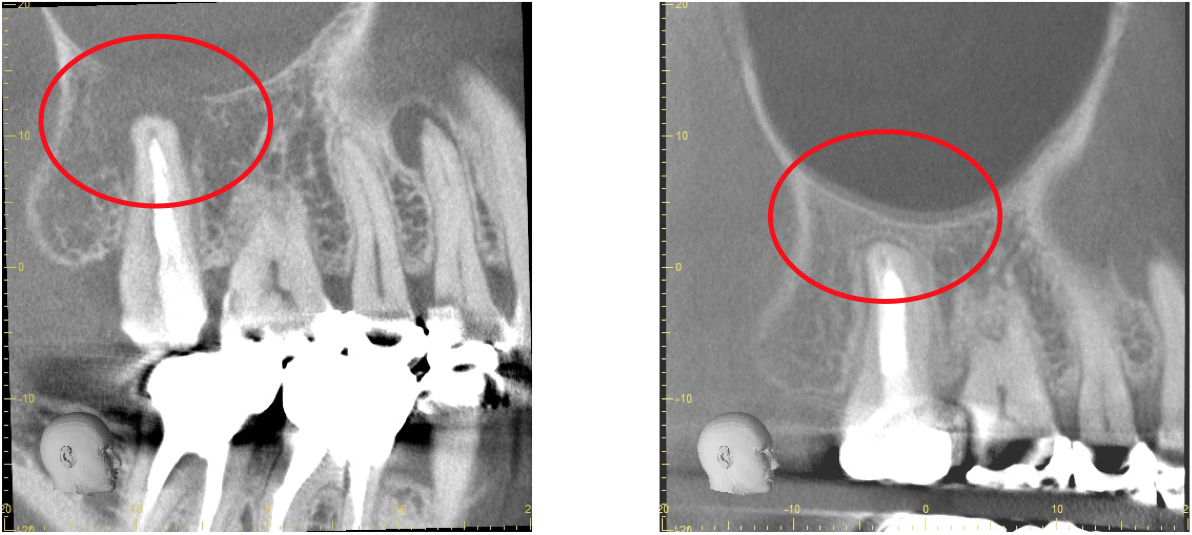

歯科用CTとは一般の医療用CTを歯科治療用に特化した装置です。

当院ではこの歯科用CTを使用して三次元で歯の構造を把握します。

任意の角度や位置から歯・顎骨を確認することもできるので治療の精度が大幅に向上します。